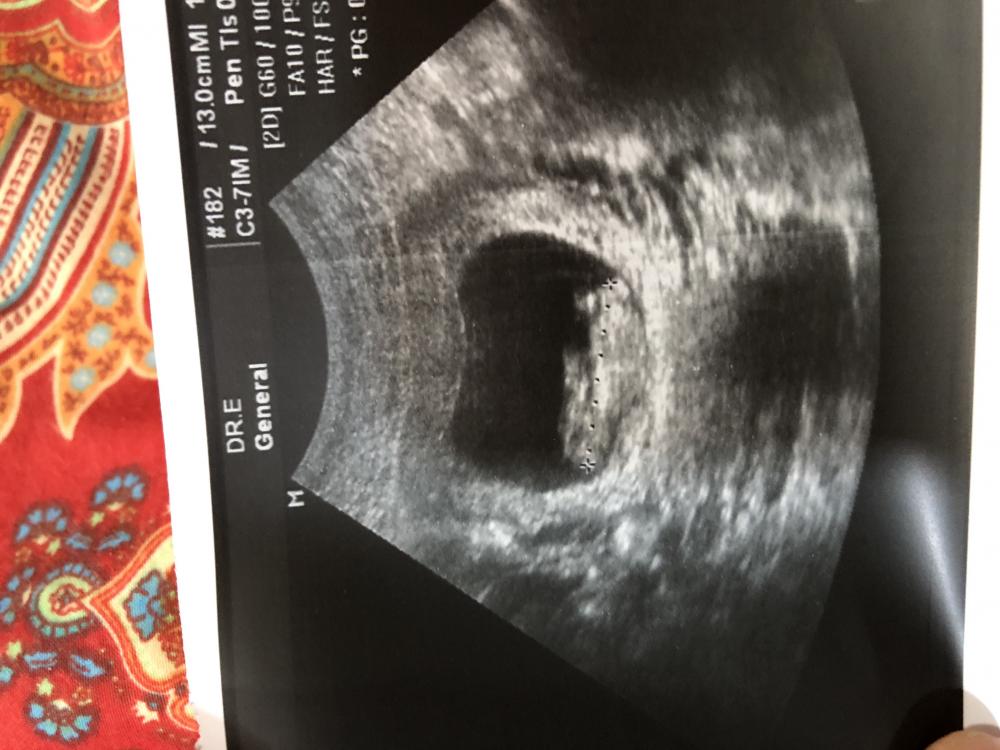

اهلا اهلا بحط صورة لسوناري في الاسبوع ١١ ويوم واحد واشوف تخمينكم لي ع اساس النظريات اللي تعرفونها اعرف ان عمر الجنين صغير لكن للتخمين فقط من خلال شكل الكيس او من خلال النظريات ..... ان شاء الله تظبط هذي المره والله يرزقك كل وحده ماتتمنى يارب يارب يارب ❤️❤️❤️

طبعا انا لااعرف لايد ولاراس ولابنكرياس في الصوره 😂😂